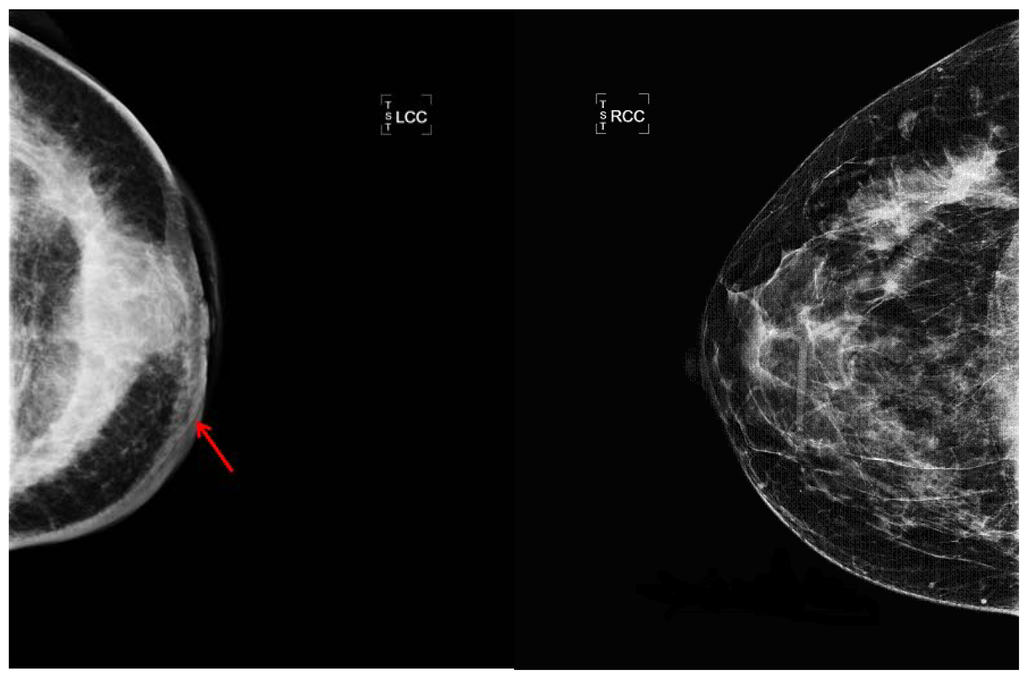

A discrete mass and thickening of the skin was the most consistent mammographic findings (Figure 2): a discrete mass was seen in 14/48 (29%) of evaluable patients and skin thickening was documented in 13 (27%). Thirty three women had sonographic examination in addition to mammography; six were concordant with mammograms revealing a discrete mass and six showed a mass on sonogram not apparent on mammography. Only one patient had a mass identified on mammogram but not on sonogram. Eighteen patients (37.5%) had no masses detectable by either mammogram or sonogram. Enlarged lymph nodes were recognized radiologically in 8 patients and asymmetric densities were also recognized in 8.

Figure 2. Radiologic photos of IBC patient. The arrow shows thickening of the skin of the left breast due to edema which is characteristic of inflammatory breast cancer. The density in IBC cases may be diffuse or localized. The other mammogram is of the uninvolved right breast.

Clinically it should be noted that reliance on mammography for the diagnosis of breast cancer in a patient with IBC requires a high index of suspicion since a discrete mass is usually not identified. More typically, secondary signs of breast cancer are present such as skin thickening and prominence of the breast trabeculae and diffuse increased density. Since mammography cannot differentiate IBC from mastitis, the reliance on additional imaging modalities such as MRI can be useful. MRI can help identify a mass which may be obscured by the increased density seen with mammography. Furthermore, MRI is a more accurate imaging approach to assess pectoral muscle involvement and may be extremely helpful in assessing response to neoadjuvant chemotherapy. Regarding therapy, the standard procedure has been well described by Bristol et al. [17] and consists of chemotherapy, surgery, more chemotherapy and radiation therapy. Forty-four of our patients followed this general protocol.